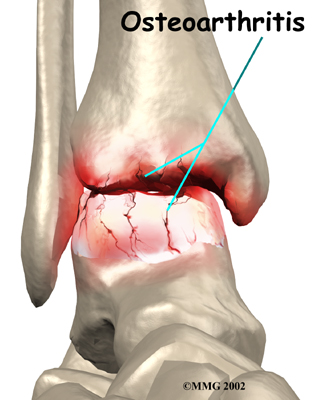

OA is usually considered a type of degenerative arthritis, or wear-and-tear arthritis. Doctors consider OA pretty much the same whether it appears years after an injury to the joint or whether it appears without any history of injury. It behaves more or less the same way.

Degenerative Arthritis

Over many years this imbalance in the joint mechanics can lead to damage to the articular surface. Since articular cartilage cannot heal itself very well, the damage adds up. Finally, the joint is no longer able to compensate for the increasing damage, and it begins to hurt. The damage occurs well before the pain begins.

In summary, arthritis may come from differences in how each of us is put together based on our genes, a condition best described as OA. Or arthritis may develop years after an injury that leads to slow damage to the joint surfaces, a condition probably best described as post-traumatic arthritis. Either way the joint is worn out, and it hurts. For the purposes of this document, we will refer to both types as OA.

Pain is the main problem with arthritis of any joint. This pain occurs at first only related to activity. Usually, once the activity gets underway there is not much pain, but after resting for several minutes the pain and stiffness increase. Later, when the condition worsens, pain may be present even at rest. The pain may interfere with sleep. The joint may swell, fill with fluid, and feel tight, especially following increased activity. As the articular cartilage starts to wear off the joint surface, the joint may squeak when moved. Doctors refer to this sound as crepitation.

When OA has reached a very severe stage, the bone itself under the articular cartilage may become worn away. This can lead to increasing deformities around the joint. In the final stages, the alignment of the bones can begin to form odd angles where they meet at the joint.